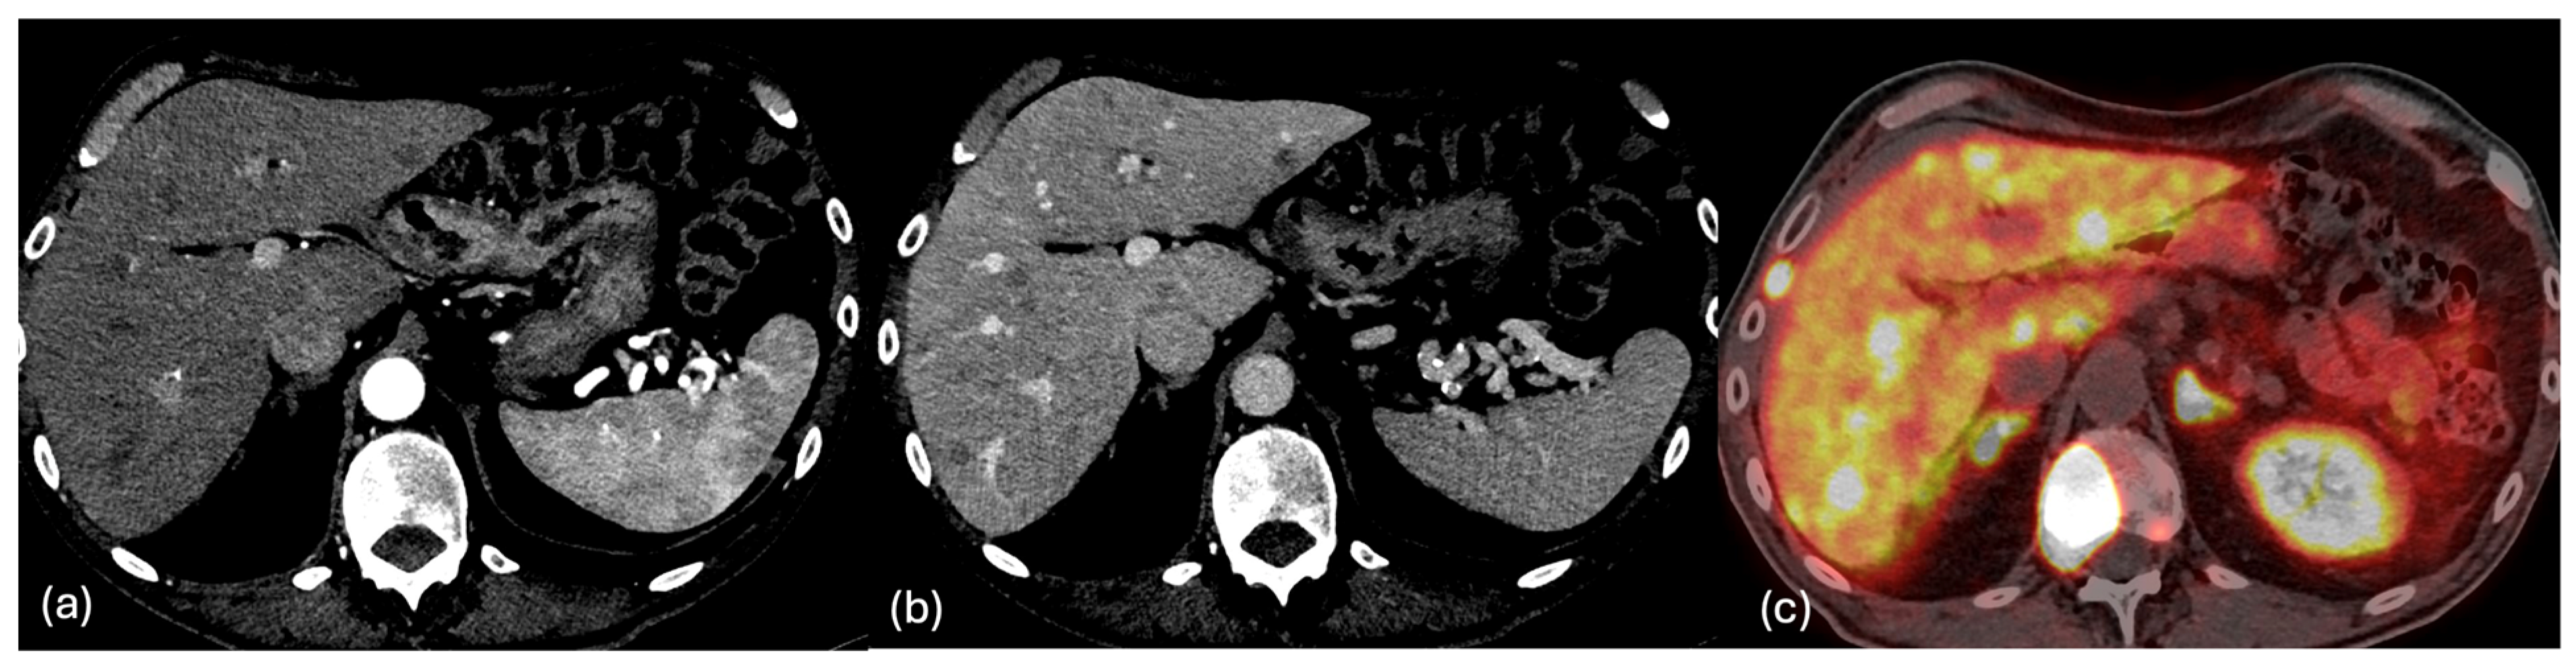

2.3. MRI

- Dromain, C.; de Baere, T.; Baudin, E.; Galline, J.; Ducreux, M.; Boige, V.; Duvillard, P.; Laplanche, A.; Caillet, H.; Lasser, P.; et al. MR imaging of hepatic metastases caused by neuroendocrine tumors: Comparing four techniques. AJR Am. J. Roentgenol. 2003, 180, 121–128. [Google Scholar] [CrossRef] [PubMed]

- Hayoz, R.; Vietti-Violi, N.; Duran, R.; Knebel, J.F.; Ledoux, J.B.; Dromain, C. The combination of hepatobiliary phase with Gd-EOB-DTPA and DWI is highly accurate for the detection and characterization of liver metastases from neuroendocrine tumor. Eur. Radiol. 2020, 30, 6593–6602. [Google Scholar] [CrossRef] [PubMed]

- Maino, C.; Vernuccio, F.; Cannella, R.; Cortese, F.; Franco, P.N.; Gaetani, C.; Giannini, V.; Inchingolo, R.; Ippolito, D.; Defeudis, A.; et al. Liver metastases: The role of magnetic resonance imaging. World J. Gastroenterol. 2023, 29, 5180–5197. [Google Scholar] [CrossRef] [PubMed]

- d’Assignies, G.; Fina, P.; Bruno, O.; Vullierme, M.P.; Tubach, F.; Paradis, V.; Sauvanet, A.; Ruszniewski, P.; Vilgrain, V. High sensitivity of diffusion-weighted MR imaging for the detection of liver metastases from neuroendocrine tumors: Comparison with T2-weighted and dynamic gadolinium-enhanced MR imaging. Radiology 2013, 268, 390–399. [Google Scholar] [CrossRef] [PubMed]

- Grazzini, G.; Danti, G.; Cozzi, D.; Lanzetta, M.M.; Addeo, G.; Falchini, M.; Masserelli, A.; Pradella, S.; Miele, V. Diagnostic imaging of gastrointestinal neuroendocrine tumours (GI-NETs): Relationship between MDCT features and 2010 WHO classification. Radiol. Med. 2019, 124, 94–102. [Google Scholar] [CrossRef] [PubMed]

- Gultekin, M.A.; Turk, H.M.; Yurtsever, I.; Cesme, D.H.; Seker, M.; Besiroglu, M.; Alkan, A. Apparent Diffusion Coefficient Values for Neuroendocrine Liver Metastases. Acad. Radiol. 2021, 28, S81–S86. [Google Scholar] [CrossRef] [PubMed]